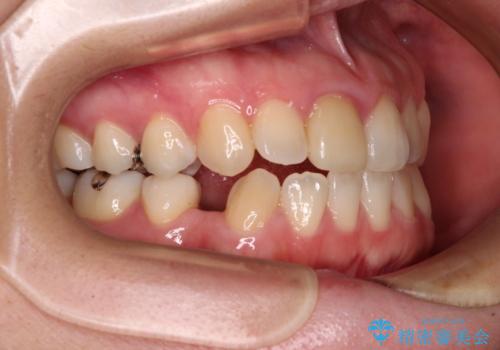

- 学生時代に行った抜歯矯正の後戻りで、隙間ができてしまったことを気にして来院された患者様です。

マウスピース矯正を検討されていましたが、後戻りの隙間が非常に大きく、奥歯を前方に移動させる必要があるため、ワイヤー装置にて矯正治療を行うこととしました。

舌の突出癖が非常に強く、その影響で隙間ができてしまったので、舌のトレーニングをしっかりと行っていただきました。